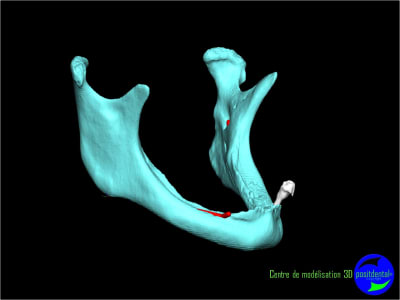

Il faut faire une ostéotomie en forme de tube au niveau de 33 et 43 et y placer deux tiges cylindro-coniques en titane. Quelques mois après tu pourras t'en servir pour fixer la prothèse.

Résorbée genre comme ça?

Sur une mandibule fortement résorbée la pose de 2 implants ne vont pas résoudre les douleurs occasionnées par la compression du nerf dentaire inférieur.